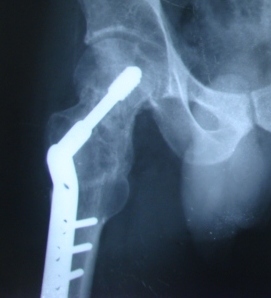

Giriraj orthopedic trauma surgeons offer treatment for these unplanned, critical events - major and minor fractures, nerve and tendon injuries, joint dislocation and other orthopedic injuries. Our surgeons provide expert, compassionate care for patients and their families in these emergencies, beginning with new, less invasive techniques for highly specialized reconstructive surgeries. As a Level One Trauma Center, Giriraj Hospital provides the highest level of emergency care in with state-of-the-art facilities and services. Our orthopedic surgeons are fellowship-trained and experts in orthopedic surgery, so our patients receive highly specialized emergency and follow-up care.

Additionally, Giriraj Hospital's high-tech imaging and surgical equipment can give patients and families choices in their treatment or therapy. For example, depending on the injury, patients may have surgical, medicinal or therapeutic options - or a combination of all three types of therapy. Our experienced Giriraj Hospital trauma team to provide comprehensive care to acutely injured patients. This multidisciplinary team includes general surgery trauma surgeons, nursing staff, mid-level providers and therapists.